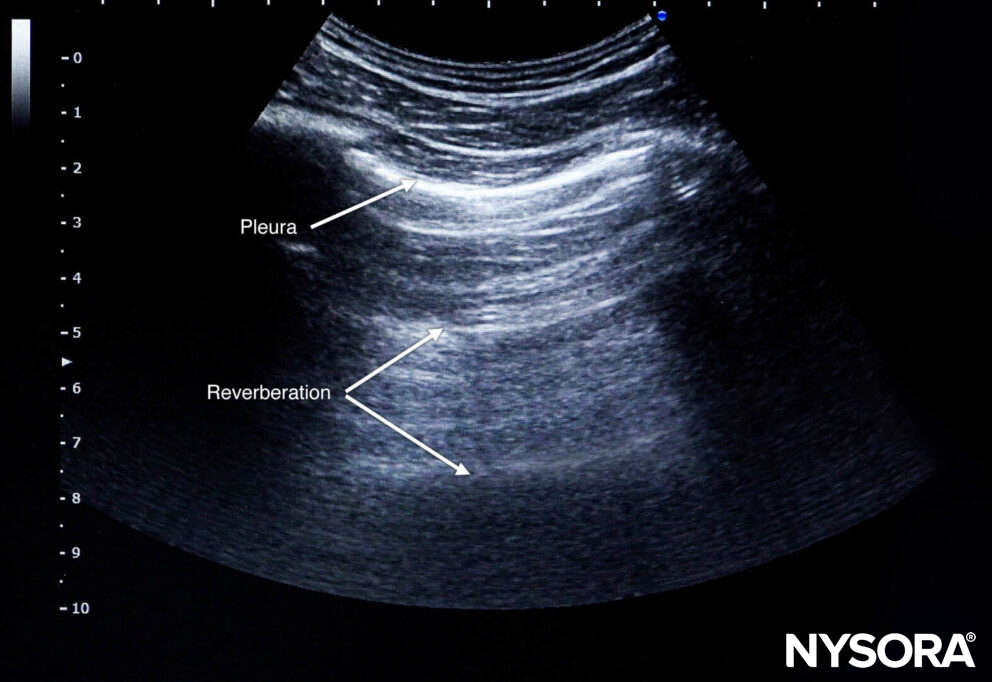

Reverberation

Reverberation is the repetitive reflection of the sound wave between two reflective layers. It will result in horizontal lines with the same interspace.

Reverberation.